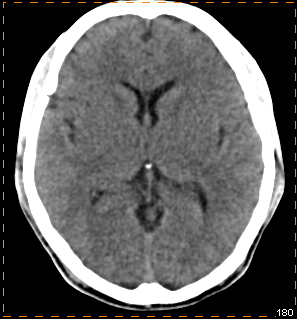

我科使用11C-CFT进行脑部多巴胺受体显像

PET/CT示:

双侧尾状核、双侧壳核放射性摄取对称,未见明显减低

根据PET图像,最终排除帕金森病